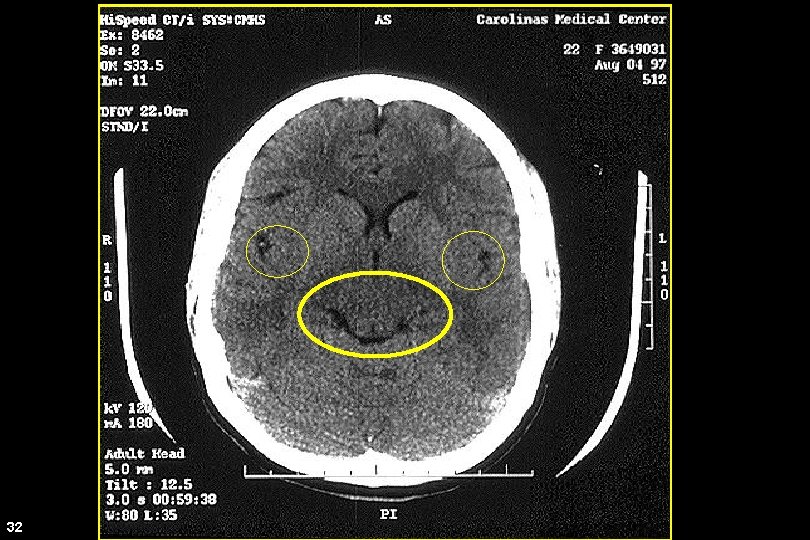

CT Scan 32

Ventricles 33 Andrew D. Perron, MD, FACEP